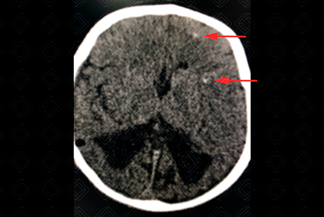

Texto alternativo para a imagem Figuras 1 e 2. Créditos: Dra. Elazir Mota - Rio de Janeiro/RJ

Descrição das figuras 1 e 2: Tomografia computadorizada nos planos axiais. Observam-se os globos oculares de dimensões reduzidas e calcificação grosseira no globo ocular à esquerda (seta na primeira imagem). Há ainda alguns focos tênues de calcificação na interface substância branca-cinzenta (setas na segunda imagem).

• Tomografia computadorizada (TC) do crânio: Quando a ultrassonografia encontra-se alterada, faz-se necessário complementar avaliação com a tomografia. Excelente método para avaliar calcificações grosseiras e aleatórias no parênquima encefálico. Permite ainda avaliação dos globos oculares (e da coriorretinite);